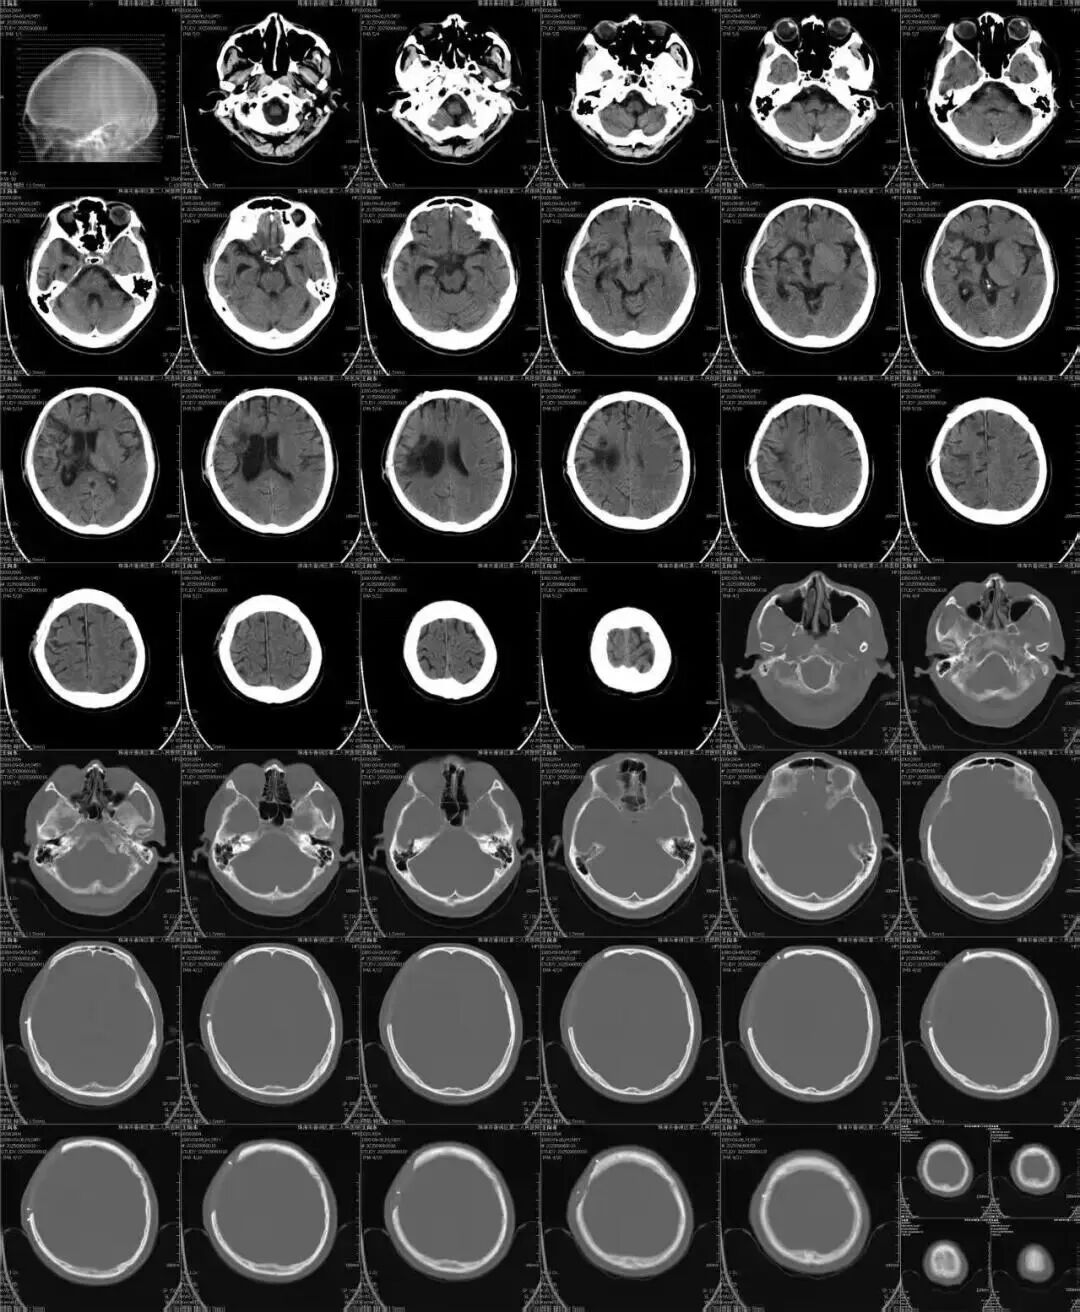

广医一院横琴医院采用CT数据,构建出患者颅骨缺损三维重建图,精准还原王先生颅骨形态,运用3D打印技术打印1:1大小颅骨实体模型,使假体与王先生的颅骨完美匹配嵌合,再根据模型打印出PEEK颅骨修复假体。随后,程国雄主任手术团队为其嵌入并固定。

影像学检查没有钛网的金属伪影,塑型完全与自身一致